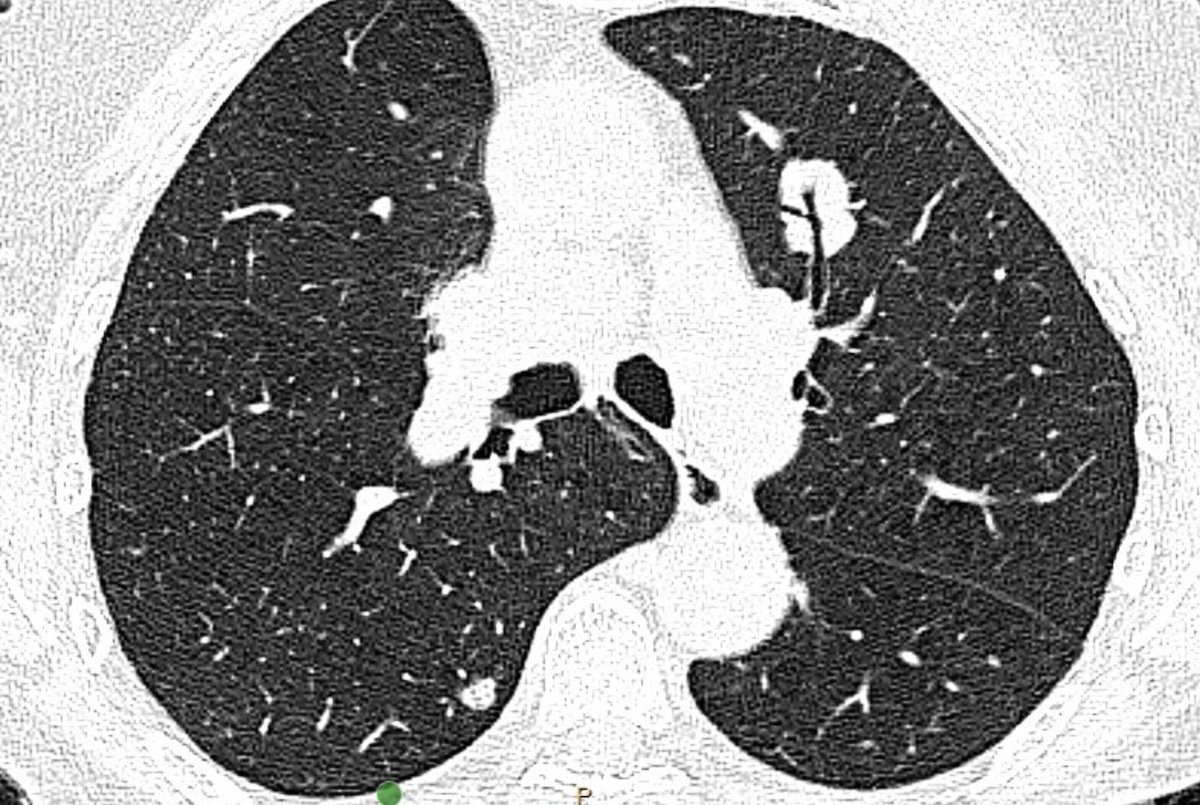

INSIDE LOOK 👀 Read from the upcoming issue (December 9): A CHEST research letter compares the currently described methods of identifying CT scan lesion location within the lung.

Read more in the journal CHEST®: hubs.la/Q03VjqGG0

#MedEd #JournalCHEST #LungCancer